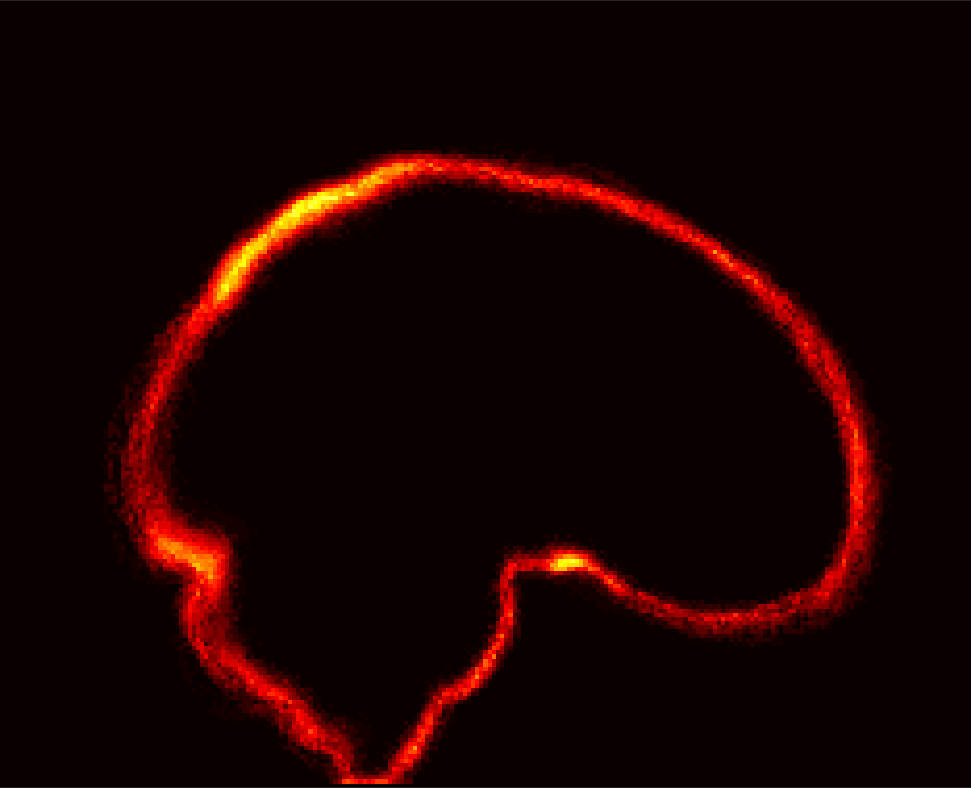

Fig. 1 shows example images from each dataset to illustrate image variability. IBSR and LPBA40 contain images from normal subjects and include large portions of the neck; BRATS has very low out-of-plane resolution; and the TBI dataset contains large pathologies and abnormal skulls.

Refer to caption

Figure 1: Illustration of image appearance variability on a selection of images from each (evaluation) database. From top to bottom: IBSR, LPBA40, BRATS and TBI.